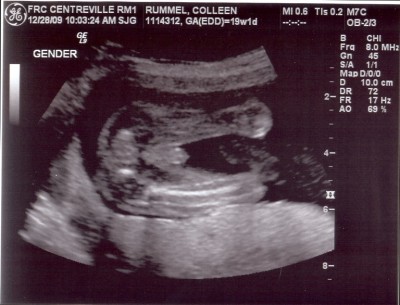

Yep, that sure is a boy! 🙂 Since you didn’t lead me astray in the daycare referral – who is your OB? Do you like him/her? I see you have Centreville on your sonogram. I had Tay in Virginia Hospital Center (Arlington) when we lived there, and my OBs are all right next door to there. Convenient for when I’m at work (I also work next door) but not so convenient for things like having babies and such. Would like to find someone down here…

So cute. And if you have to ask what he’s doing back there, you probably don’t want to know.

So adorable! I can’t wait to see what this baby boy looks like on the outside!